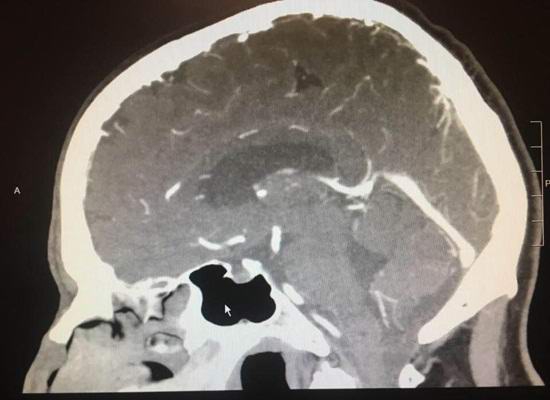

Paul Wood, a Lodai városában élő, fejfájással kezdte panaszkodni fájdalom néhány hónappal ezelőtt. Amikor egy amerikai fordult kórházban, agydaganatát diagnosztizálták. Hozzárendelt egy kockázatos a műtét azonban egy nappal azelőtt hirtelen kiderült, hogy a daganat egyszerűen eltűnt. Az orvosok nem hitték a szemüket, mikor A röntgen azt mutatta, hogy a beteg agya egészséges lett állam.

A szakemberek elismerik, hogy ritka esetekben rosszindulatúak a daganat önmagában kezdhet visszafejlődni akár teljes eltűnés. Bármely materialista számára megfontolások szerint ez nem történhet meg egy nap alatt.